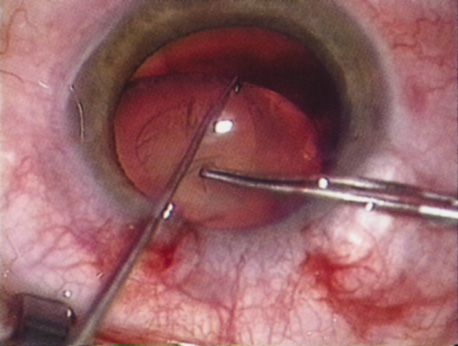

HYDRODISSECTION

Hydrodissection can be performed after the surgeon has successfully completed capsulorrhexis.97 If the capsulorrhexis is not intact, fluid forced around the interior of the capsule may cause the bag to splay open. With capsulorrhexis, hydrodissection is a safe and extremely useful maneuver. Hydrodissection can be thought of as two maneuvers: hydrodelineation and cortical cleaving hydrodissection. By placing a 27-gauge cannula on a syringe filled with balanced saline solution (BSS), the surgeon can direct fluid beneath the residual anterior capsular rim to create a cleavage plane. Depending on the direction the fluid wave takes, different lamellae of the cataract will be separated. Hydrodelineation is the term used when the cleavage plane separates the adult nucleus from the fetal nucleus or the adult nucleus from the more peripheral epinucleus. Hydrodelineation often results in the characteristic golden ring sign (Fig. 11). Cortical cleavage occurs when the cortex is separated from the capsular bag (Fig. 12). Finding the cortical cleavage plane may be facilitated by gently lifting the capsular margin away from the cortex with the BSS cannula before injecting. Several small bursts of fluid allow the surgeon to monitor progress of the fluid wave. When dealing with a soft nucleus, the authors strive to perform true cortical cleaving hydrodissection. For a hard nucleus, hydrodelineation allows manipulation of less of the nuclear bulk, although the remaining epinuclear shell must be addressed in an additional step. Hydrodelineation is particularly useful if the nucleus is not freely mobile after cortical cleaving hydrodissection.

Fig. 12. Hydrodissection, performed subincisionally with a 27-gauge J-cannula, produces a cleavage plane between the capsule and the cortex. The small blue arrows indicate the advancing fluid wave.